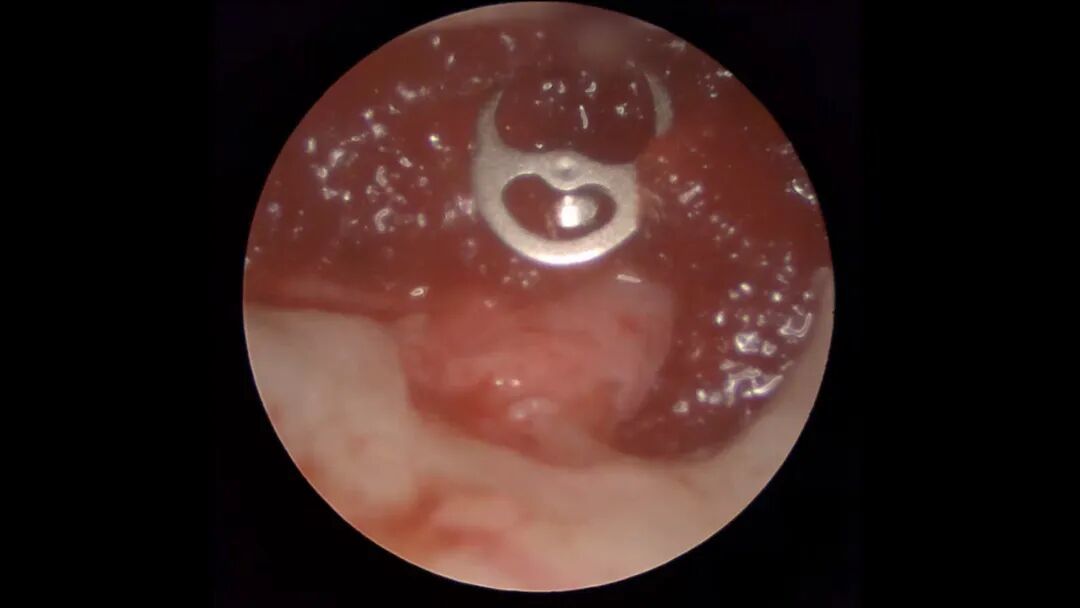

左耳术前报告

术前鼓膜穿孔,鼓室潮湿,残余鼓膜肿胀

在向刘大爷耐心解释病情、详细说明手术方案后,尽管老人对手术心存担忧,但基于对耳鼻喉科团队专业能力的信任,最终决定接受 “鼓室成形术+部分听骨植入术”。术前,手术团队依据CT影像精准规划手术路径,明确病灶范围与听骨链破坏程度,为手术安全开展做好充分准备。